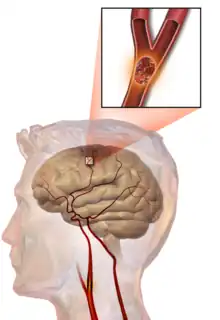

- ACV o ictus isquémico o infarto cerebral: una isquemia (disminución importante del flujo sanguíneo) en el cerebro, de manera anormalmente brusca; el flujo sanguíneo deficiente al cerebro termina produciendo muerte celular.[4]

- ACV o ictus hemorrágico, derrame cerebral o hemorragia cerebral: la hemorragia originada por la rotura de un vaso cerebral.

Ictus isquémico

Un ictus isquémico o ataque cerebrovascular oclusivo, también llamado infarto cerebral, se presenta cuando la estructura pierde la irrigación sanguínea debido a la interrupción súbita e inmediata del flujo sanguíneo, lo que genera la aparición de una zona infartada y es en ese momento en el cual ocurre el verdadero infarto cerebral, y se debe solo a la oclusión de alguna de las arterias que irrigan la masa encefálica, ya sea por acumulación de fibrina o de calcio o por alguna anormalidad en los eritrocitos, pero generalmente es por arteriosclerosis (también ateroesclerosis, de ateroma) o bien por un émbolo (embolia cerebral) que procede de otra localización, fundamentalmente el corazón u otras arterias (como la bifurcación de la carótidas o del arco aórtico). La isquemia de las arterias cerebrales puede producirse por los siguientes mecanismos y procesos:

En un ictus trombótico o aterotrómbico, se forma un coágulo (trombo) en una de las arterias que irrigan el cerebro, lo que provoca la isquemia; este fenómeno se ve favorecido por la presencia de placas de aterosclerosis en las arterias cerebrales.

Ictus embólico

Ictus hemorrágico

Se deben a la rotura de un vaso sanguíneo encefálico debido a un pico hipertensivo o a un aneurisma congénito. Pueden clasificarse en: intraparenquimatosos y hemorragia subaracnoidea.